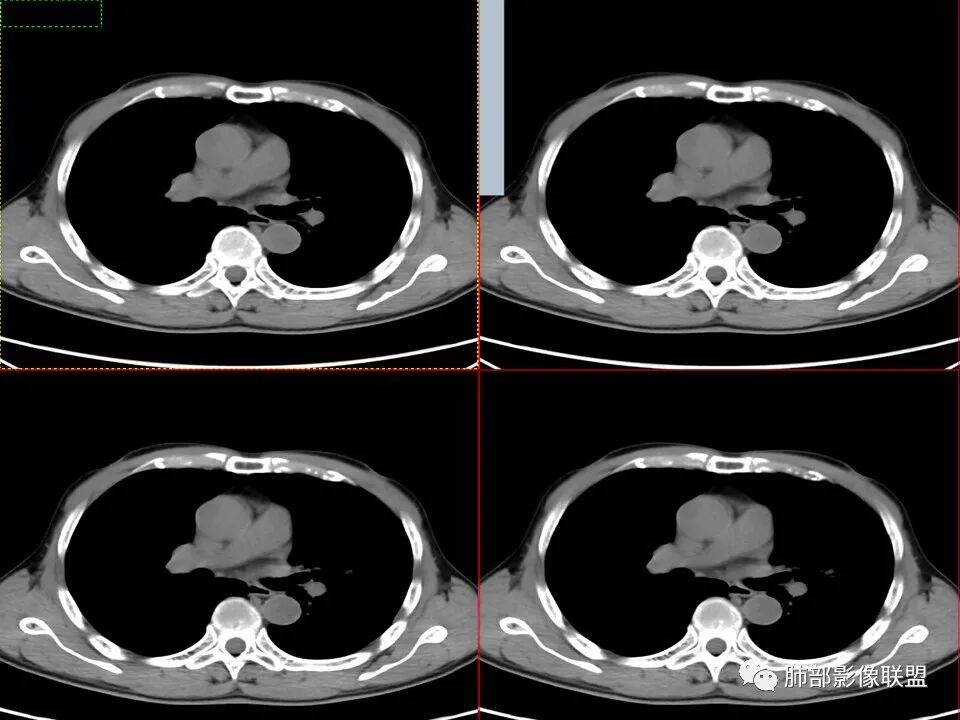

左肺上叶舌段近肺门区不规则结节,密度较均匀,结节边缘平直为主,可见粗短毛刺、毛刺偏软,浅分叶,收缩力不强,膨隆也不明显,周围可见模糊GGO,病灶内部支气管显示不清,病变远端支气管明显扩张,病灶与叶间裂呈宽基底相连,见刀切征,并见叶间裂多发结节影,叶间裂未见明显移位。

患者推测中老年人,无明显临床症状,肺气肿背景不明显,虽然病灶整体炎性征象较多,叶间胸膜多发结节,常规要考虑结核和腺癌,PET-CT肿瘤和炎性病变都可以高摄取,敏感性高,但特异性不高,而且腺癌周围缺乏清晰的磨玻璃及收缩力不强,故暂不考虑;虽然左肺上叶舌段病灶与支气管关系密切,如果周围磨玻璃推测为早期的阻塞性炎症,还有CYFR轻度升高,鳞癌不能除外,但是病灶的整体形态比较符合炎性改变。本病例可惜未行CT增强扫描,无法观察结节的强化特点及病灶内血管走行情况。